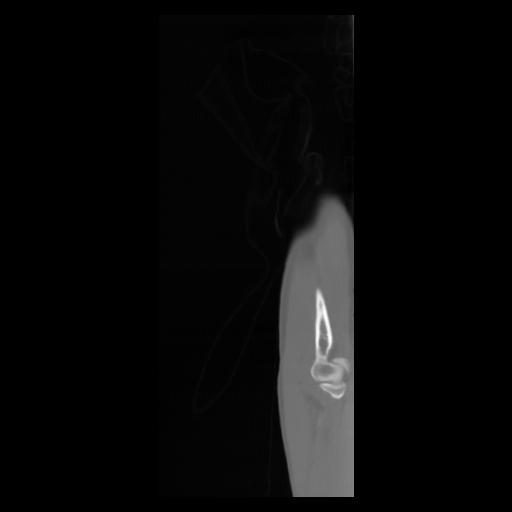

30 CUERPO,CE,Sagittal,3.000,CUERPO,Sagittal,